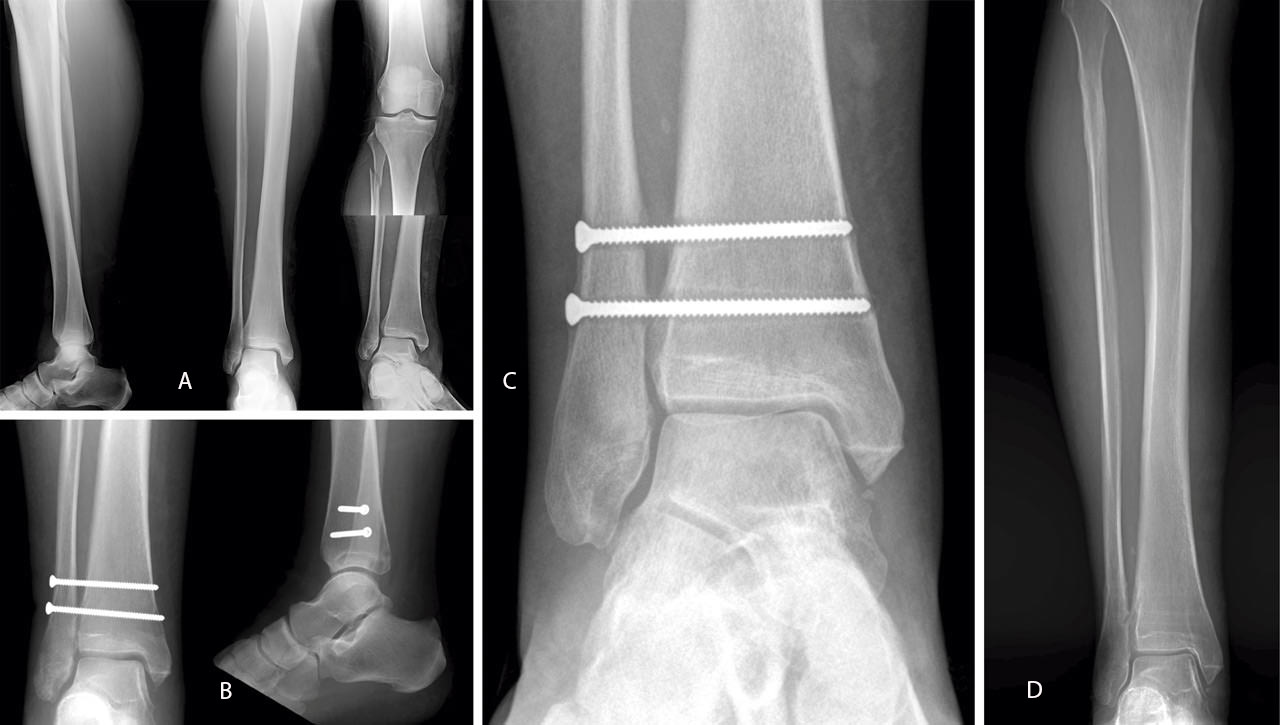

En lesiones ligamentosas acompañadas de fractura, lesiones por PRE (Weber C) o SER (Weber B), se realiza la fijación con un solo tornillo supra- o transindesmal. En lesiones ligamentarias puras con inestabilidad franca de la sindesmosis se añade un segundo tornillo proximal, paralelo al anterior(3)(13)(31)(Figura 3).

Figura 3. Mujer de 52 años con fractura de Maisonneuve tras caída por escaleras (A); fijación con 2 tornillos tetracorticales de 3,5 mm (B); osteolisis tras inicio de la carga total (C); retirada de tornillos 6 meses tras la intervención quirúrgica (D).